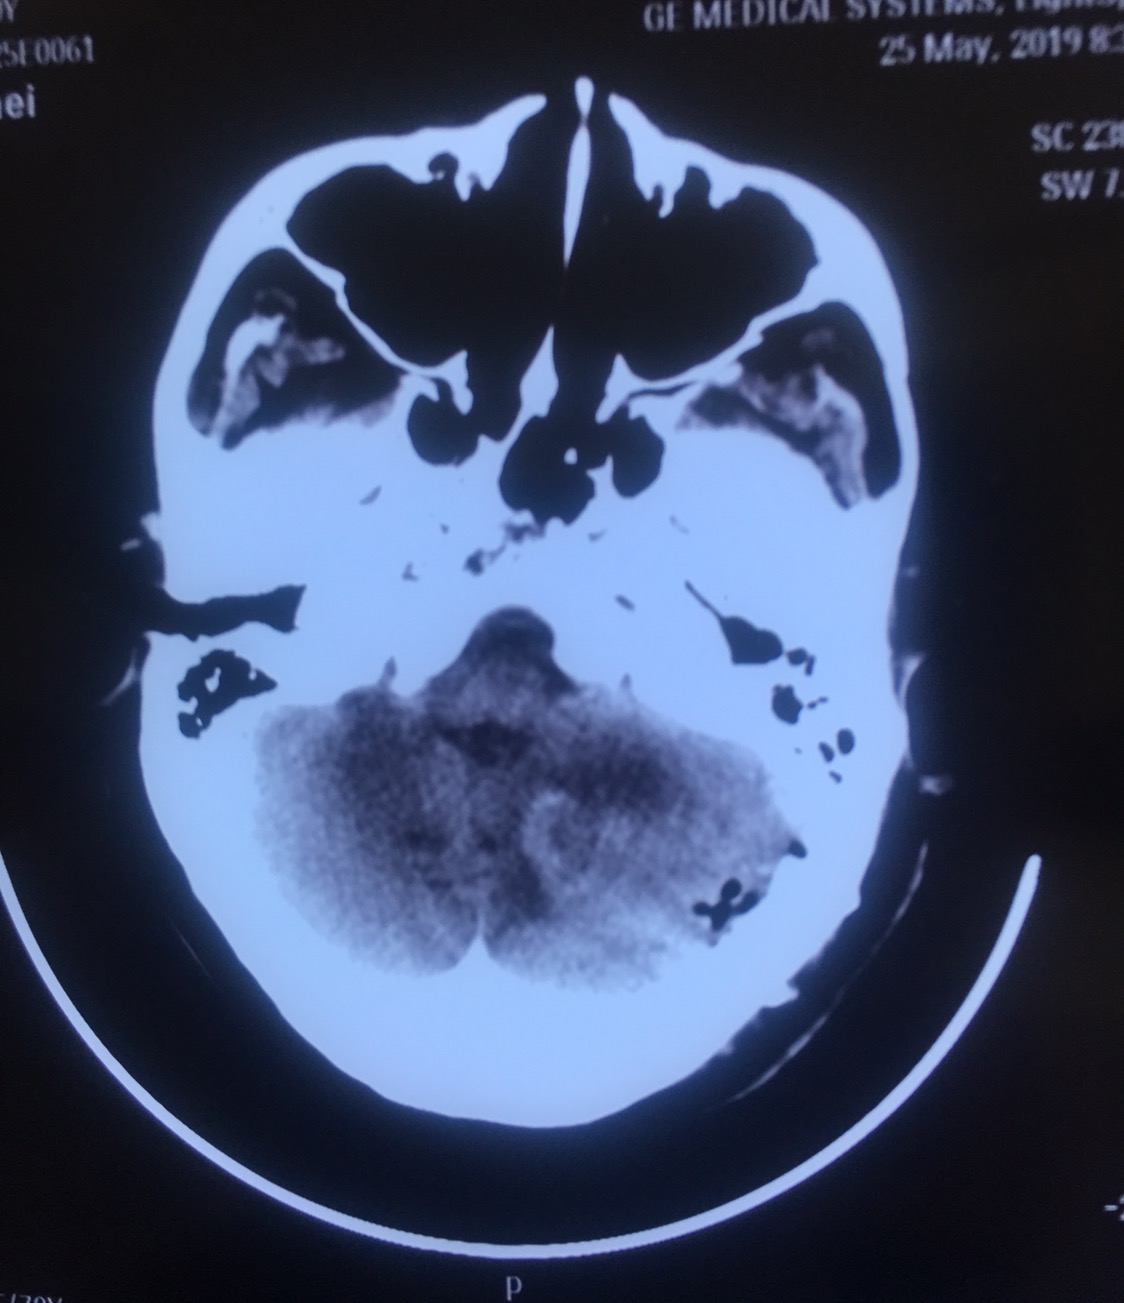

患者周某,女,70岁,以“间断头痛伴恶心呕吐五天”为主诉入院。既往患有高血压病3年,糖尿病3年,冠心病2年,控制情况一般。查体:神志模糊,精神差,可对答,回答正确,能完成简单指令性动作,反应迟钝,双瞳孔等大等圆,直径约3mm,光反射灵敏。指鼻试验不准,轮替试验缓慢。跟膝胫试验不稳。病理反射未引出。诊断:1.左侧小脑实性血管母细胞瘤,2.梗阻性脑积水,3.高血压病,4.冠心病,5.2型糖尿病。

增强轴位

增强冠位